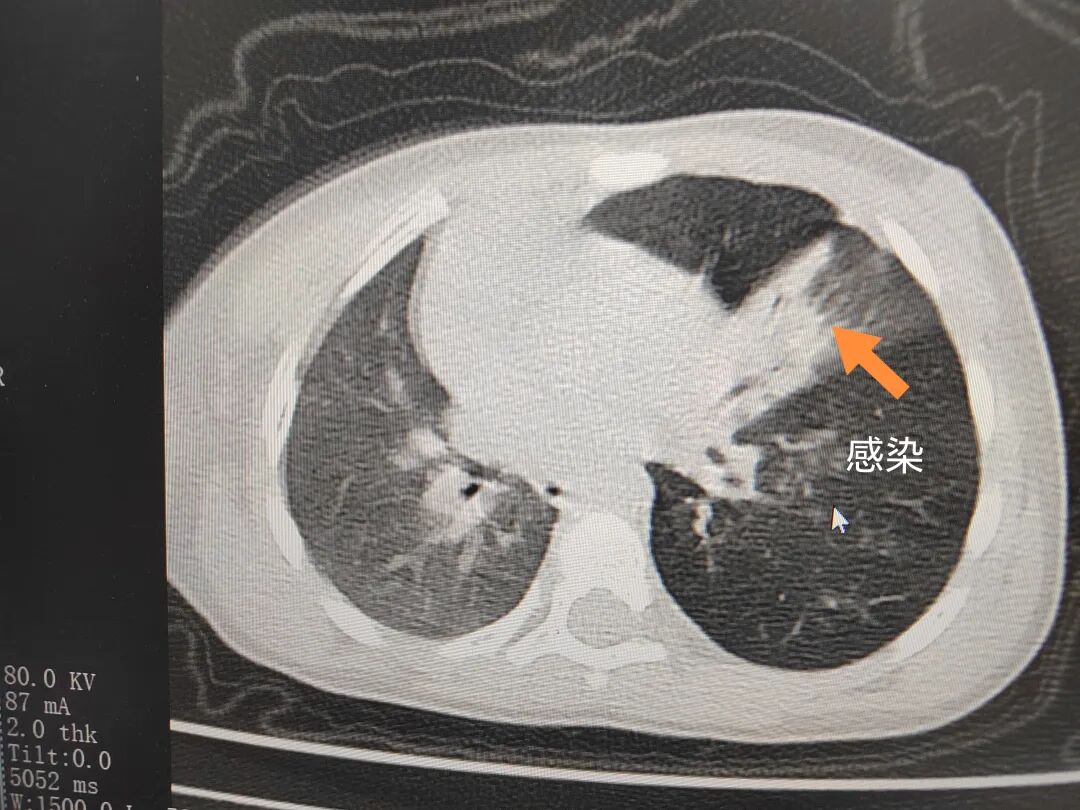

三天后(11月13日),趙寶出現(xiàn)高熱、咳喘加重,家長著急了,再次帶他來到醫(yī)院。CT檢查顯示左肺過度充氣,左肺上下葉支氣管主干見不規(guī)則高密度影,左肺上葉可見大片狀密度增高影,縱隔窗實(shí)變,提示為“左側(cè)支氣管內(nèi)異物并繼發(fā)性改變,左肺上葉舌段肺膨脹不全”。

市二院小兒呼吸內(nèi)科團(tuán)隊迅速為患兒制定了周密的手術(shù)方案,并很快安排了氣管鏡探查。術(shù)中,主治醫(yī)師田慧等憑借嫻熟的氣管鏡操作技術(shù)成功將異物大塊板栗取出。由于板栗在氣管內(nèi)存留時間較長,質(zhì)地軟糯易碎,大大增加了手術(shù)難度。檢查還發(fā)現(xiàn),異物停留部位的氣管黏膜已出現(xiàn)充血紅腫、糜爛,導(dǎo)致患兒住院時間相應(yīng)延長。此次事件給趙寶的家庭帶來了不小的驚嚇與擔(dān)憂,也再次為廣大家長敲響了警鐘。

市二院小兒呼吸內(nèi)科副主任楊亞娟介紹,異物誤入氣道可能導(dǎo)致氣道阻塞,嚴(yán)重時可引發(fā)窒息,甚至危及生命。若異物進(jìn)入支氣管,造成不完全堵塞,可引起阻塞性肺氣腫;如完全堵塞支氣管,則可能導(dǎo)致肺組織萎縮,形成肺不張。此外,若異物存留時間較長,或?yàn)橹参镄援愇?,容易合并?xì)菌感染,產(chǎn)生膿性分泌物,進(jìn)而發(fā)展為肺炎。她強(qiáng)調(diào),盡早診斷并取出異物,是減少并發(fā)癥、降低病死率的關(guān)鍵。